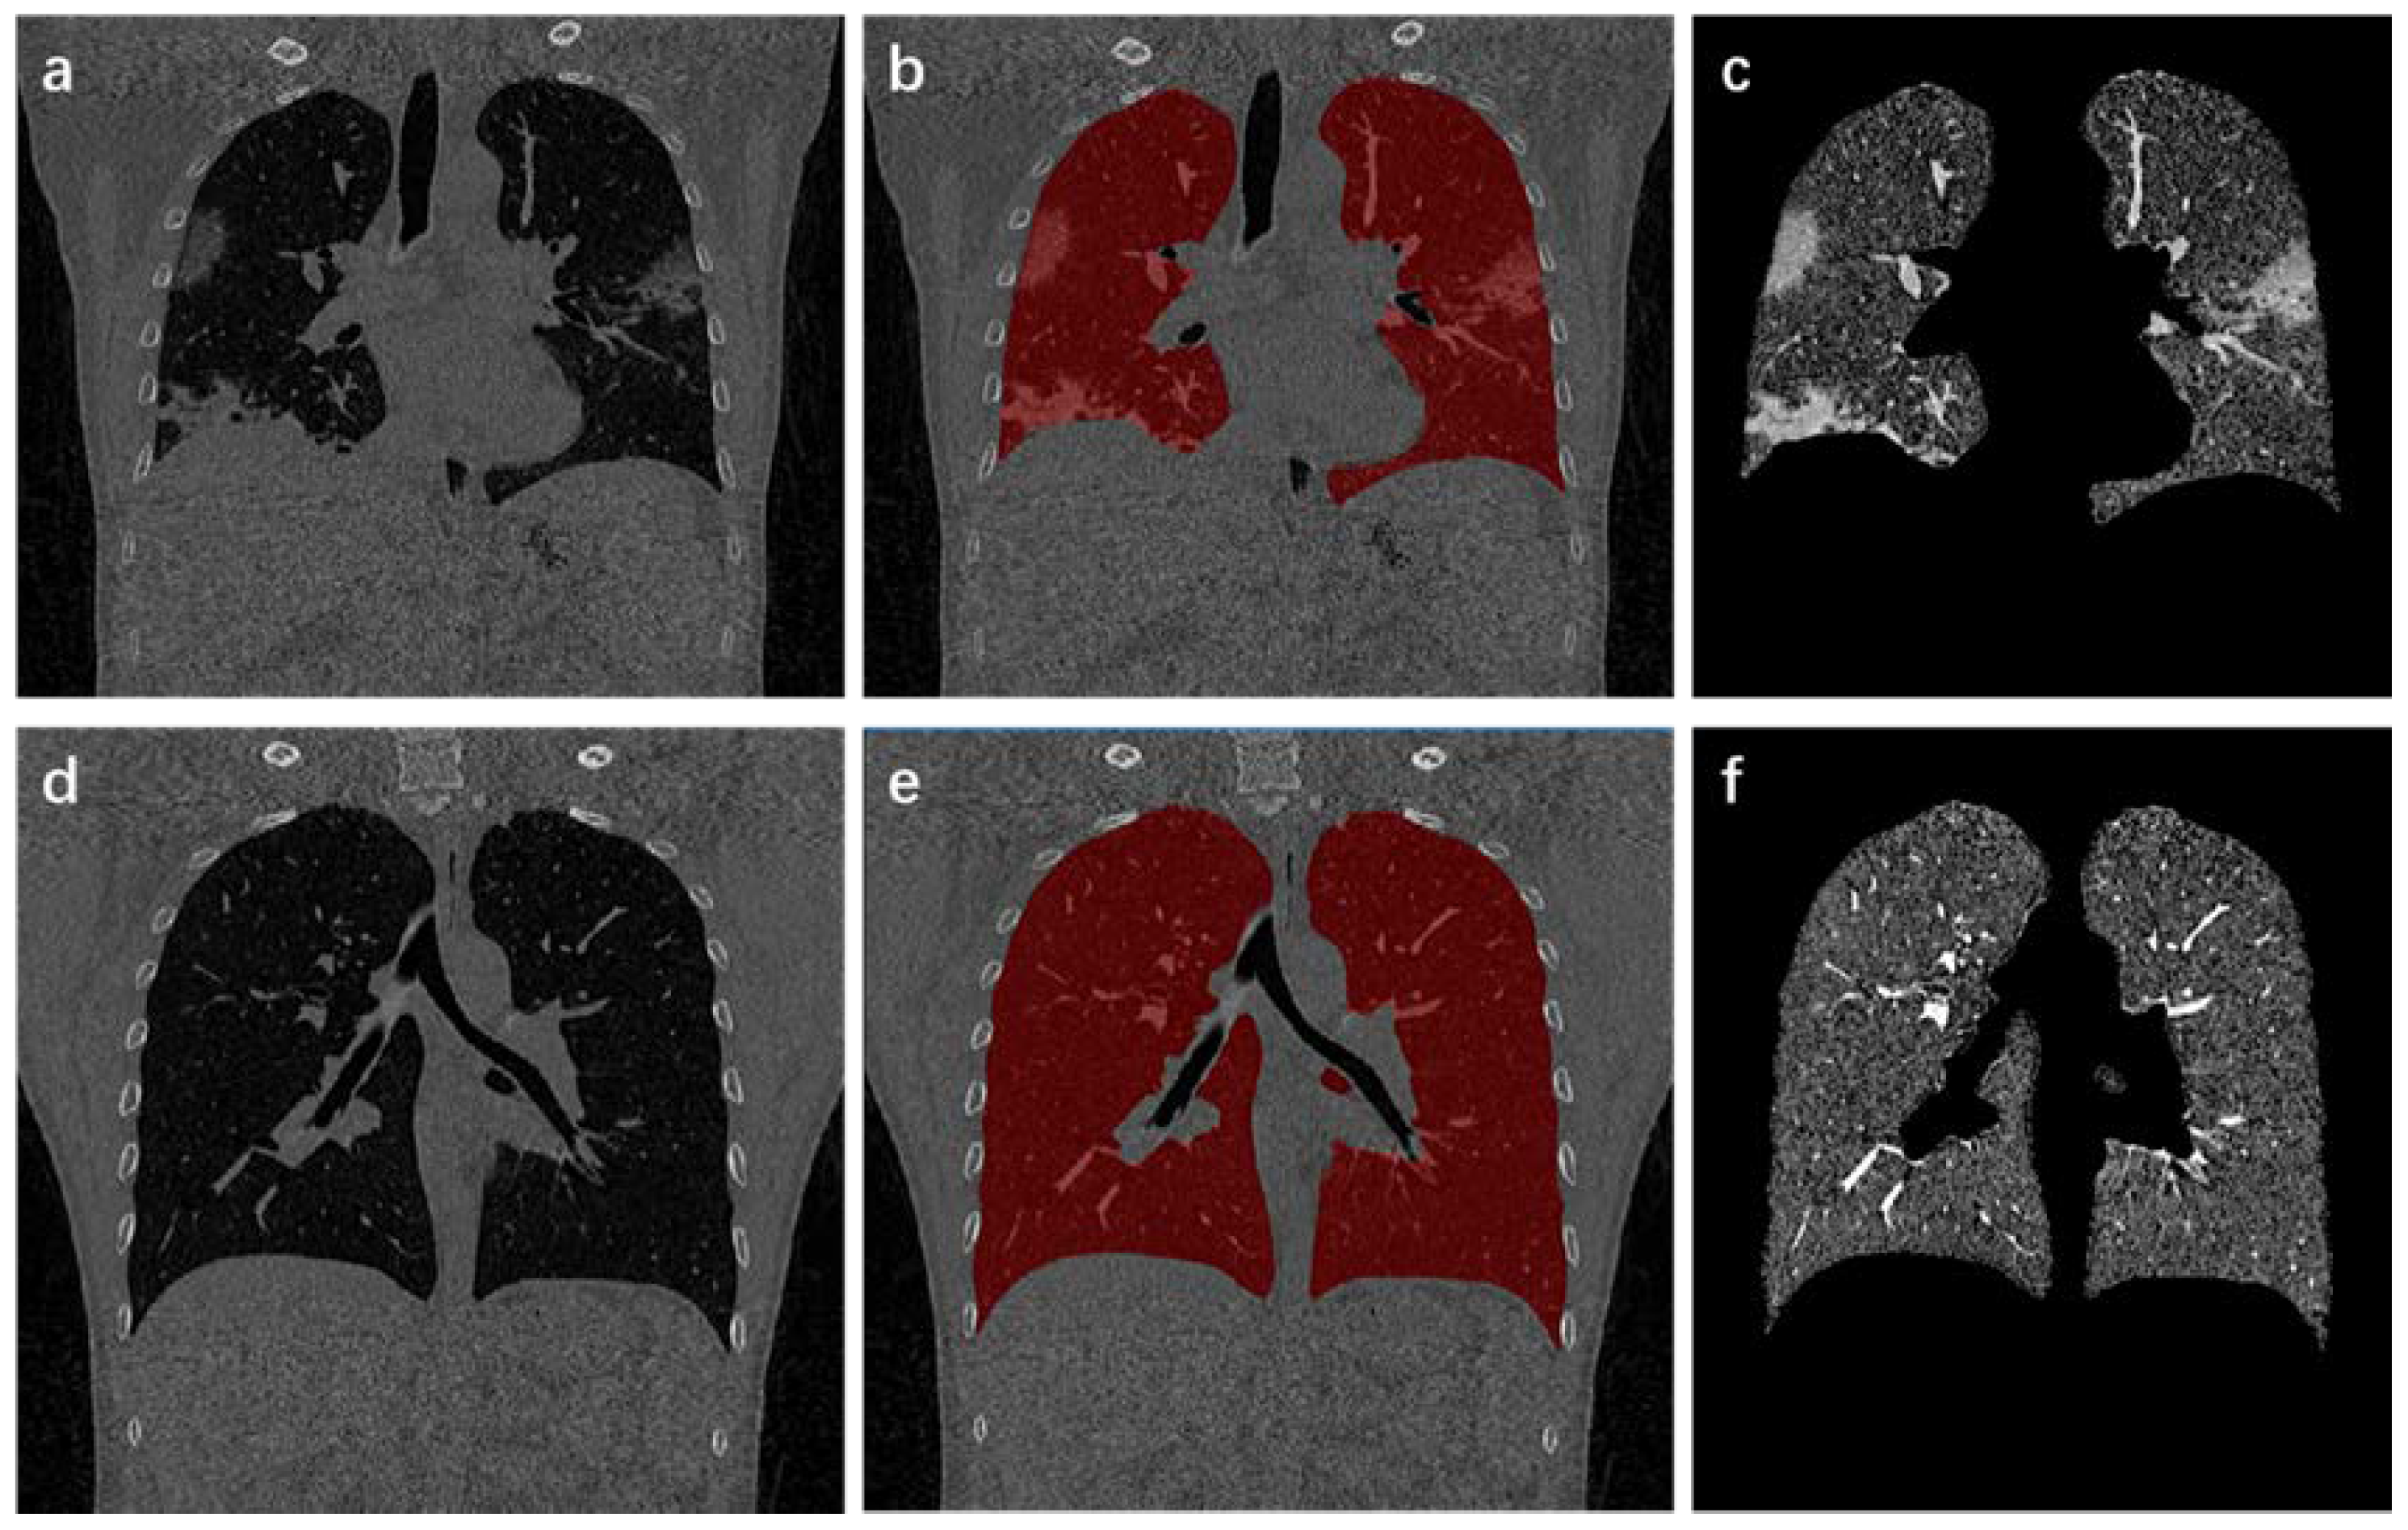

Figure 3.

Process and results of lung region extraction. (a,d) are the original CT images; (b,e) show results of lung mask covering the original CT images; (c,f) indicate the extracted lung area.